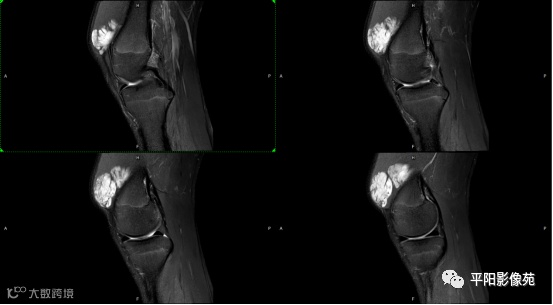

影像表现:

左膝关节股内侧肌内见多房样短T1长T2信号,内可见分隔,增强扫描明显强化,分隔未见明显强化,病灶局部与股骨远端分界不清。

MRI表现:好发于下肢, 较大病灶多为与肢体长轴一致的梭形, 边缘不清, 较小病灶呈类圆形, 边缘较清;②T1WI呈等或稍高信号, 病灶内部或边缘可见线条状或花边状高信号灶, 类似于皮下脂肪信号, T2WI上为明显高信号, 为本病特征性MRI表现;③病灶内静脉石及血管流空影为又一特征MRI表现;④GD-DTPA增强, 病灶明显强化, 其内低信号间隔无强化;⑤可见骨外形改变, 骨质增生及骨质吸收等表现。